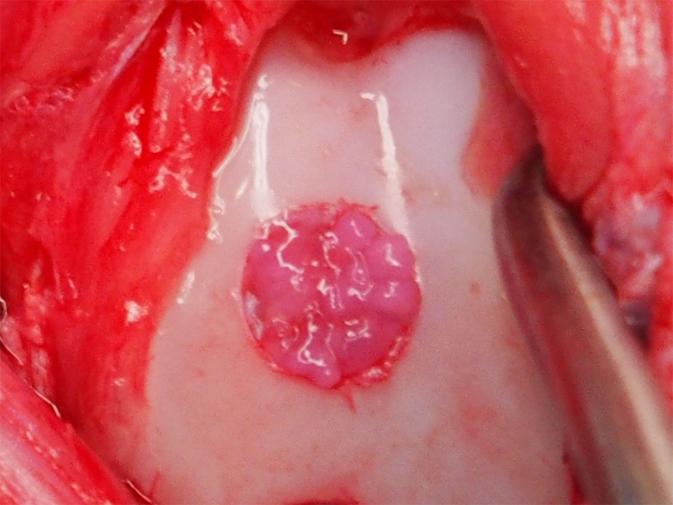

Another advantage to this method is that it avoids the use of artificial scaffolds. In other studies on ES cell- and iPSC-derived chondrocyte transplantation, artificial scaffolds are included into the transplant to provide support until the chondrocytes begin secreting their own ECM proteins. However, it is unclear if artificial materials prevent optimal integration into the cartilage. Because the chondrocytes have already begun secreting ECM proteins, they can be transplanted without scaffolds. This feature is attributed to the use of a suspension culture and medium that included BMP2, TGFβ1 and GDF5 for six weeks. After this time, chondrocytes stopped proliferating and began secreting hyaline cartilage ECM proteins with high purity. This mix of chondrocytes and ECM matrix proteins was harvested as particles 1-2 mm in diameter that could be directly transplanted into the injured tissue (Image 1&2). Each particle contained approximately 70,000 chondrocytes, which according to Tsumaki is good reason to believe enough cells for human transplantation is feasible. "One million chondrocytes are needed to treat 1 cm2 defects, and the area of a typical defect is 2-10 cm2. So, we are considering transplanting 30-150 particles. These numbers are quite manageable."